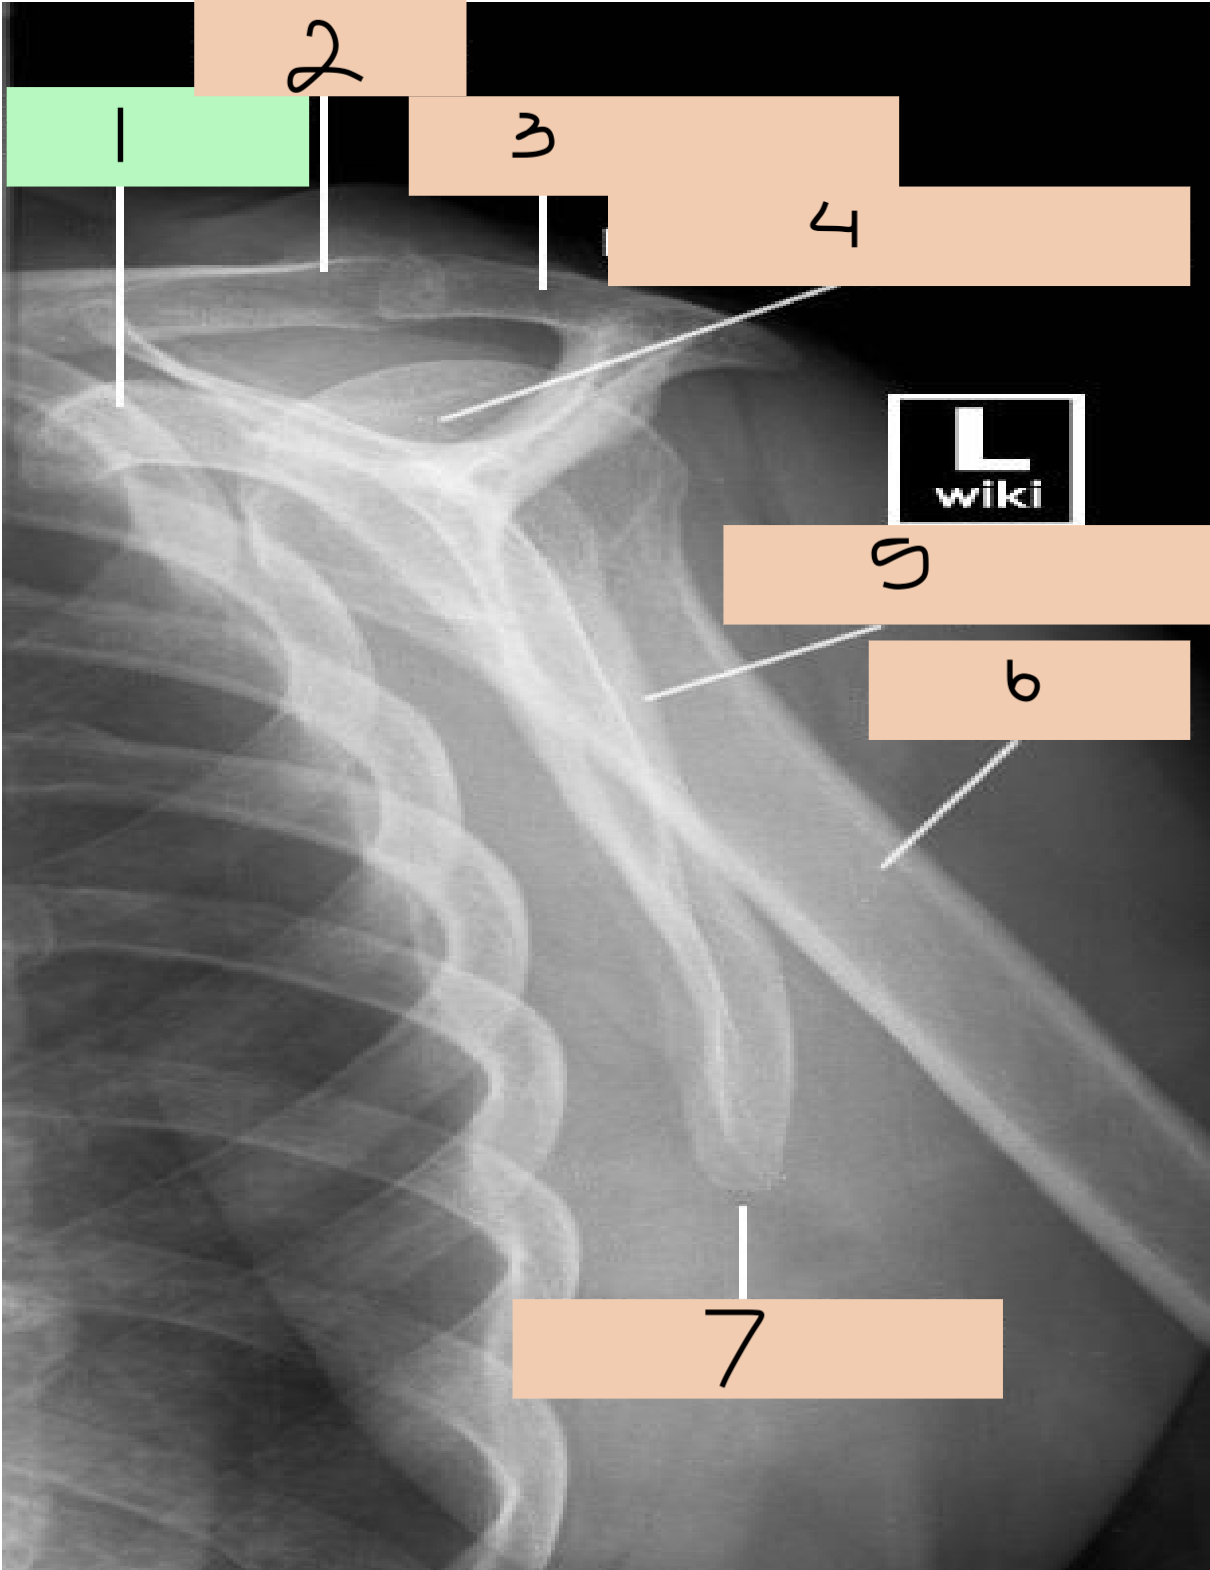

1

coracoid process

2

clavicle

3

acromion process

4

humeral head

6

glenoid

7

body of scapula

8

lateral border of scapula